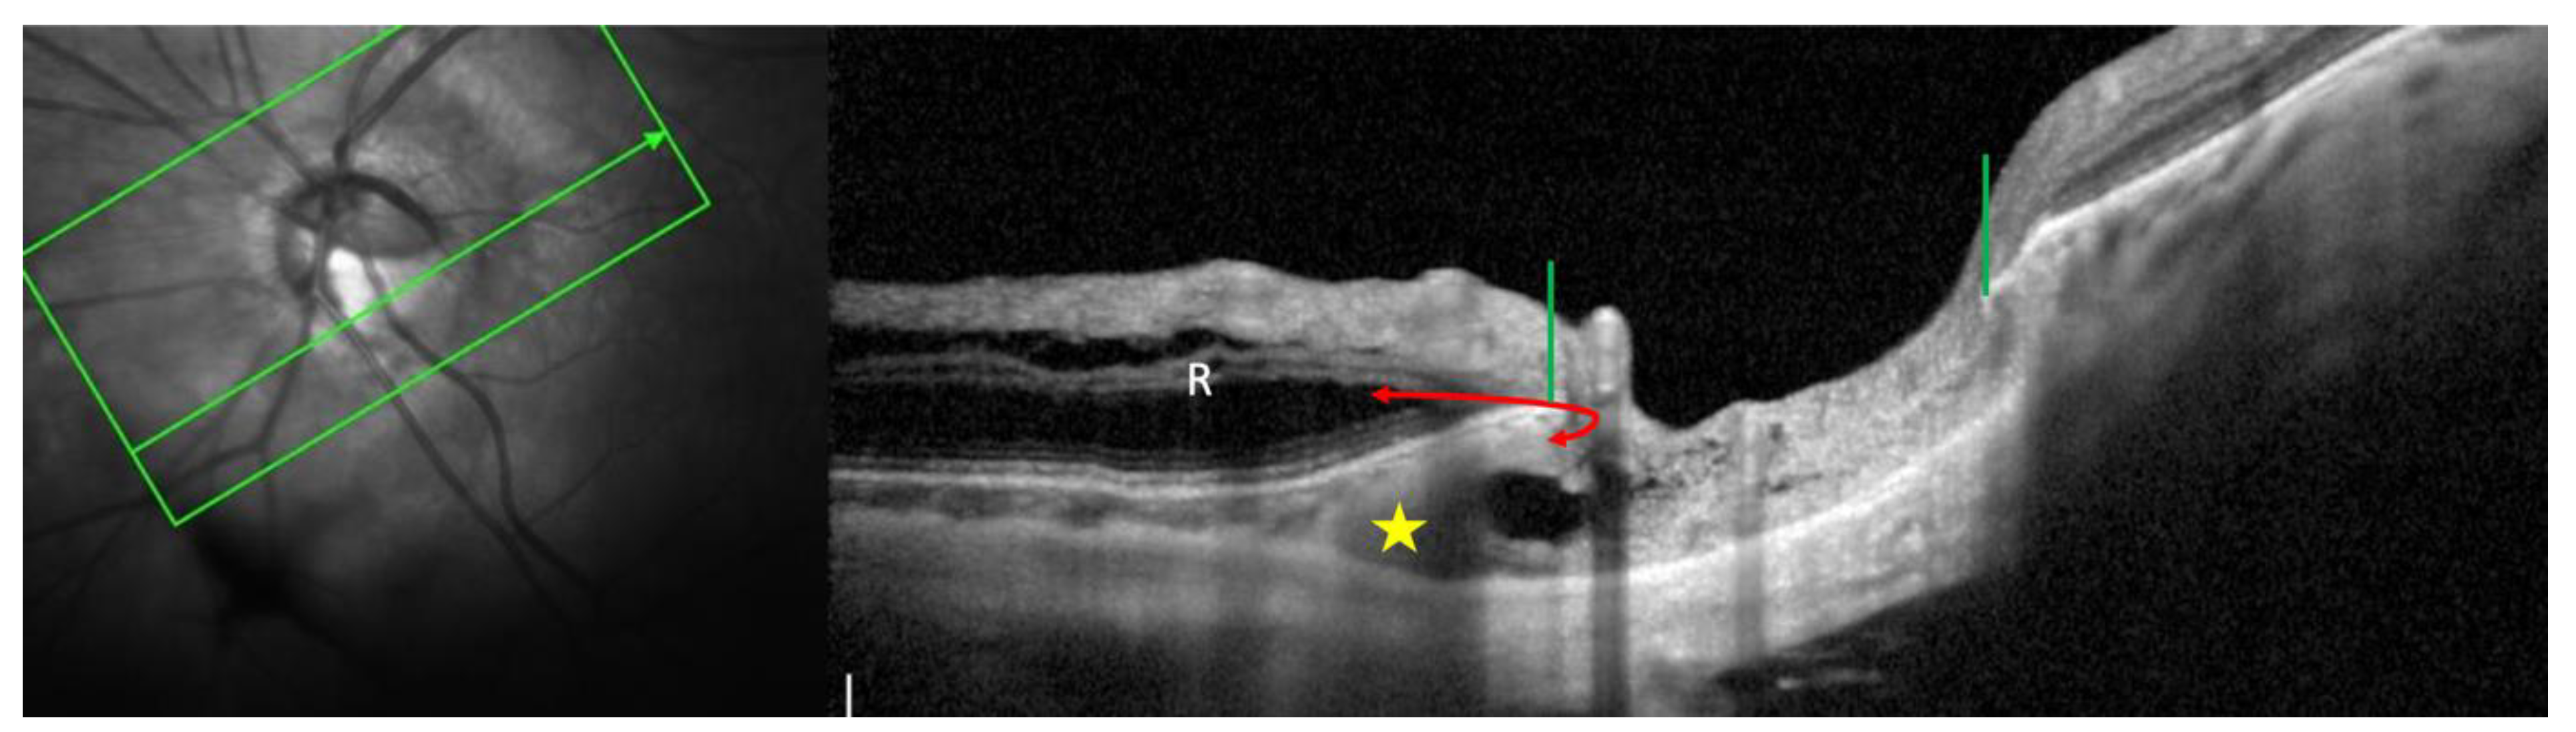

| 2022 Ehongo [16] |

Objective: To compare the peripapillary polar regions in eyes with gamma PPA and PPS in the presence or absence of PICC Design: Observational cross-sectional study, Examinations: fundus pictures, serial SD-OCT |

PICC is a suprachoroidal detachment. PICC is aligned with the subarachnoid space. PICC is detected up on the visualisation of the ON sheaths. |

Hypothesis: The pulling of ON sheaths on the scleral flange during eye movements would promote PICC. | Confirmation that PICC is as suprachoroidal detachment. Suggestion that it is promoted by tractions of the ON sheaths during eye movement. |